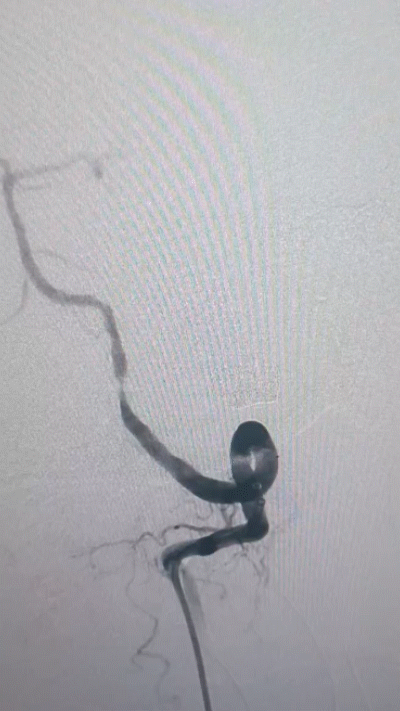

Tethys®中间导引导管沿导丝顺利到达病变近端附近,锁骨下至椎动脉转弯处充分体现了近端良好的⽀撑性与抗折性,帮助后续⾎管开通治疗建⽴稳定通路系统

中间导管到位后造影

复查造影

术后造影